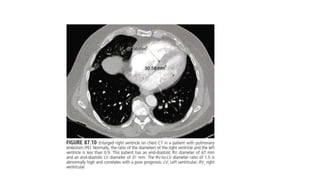

DIAGNOSTIC TESTS CT Angiography •Studies have shown sensitivity of close to 95% with an experienced observer • One of the most commonly cited benefits of CTA is its ability to detect alternative pulmonary abnormalities that may explain the patient's symptoms and sign • It allows adequate visualization of the pulmonary arteries down to at least the segmental level. • Contrast enhanced MDCT-PA is currently the preferred method of diagnosis.

• 39.

• RV toLV dimensional ratio of 0.9 or greater • IVS septal bowing towards LV • Reflux of contrast medium into inferior venacavae